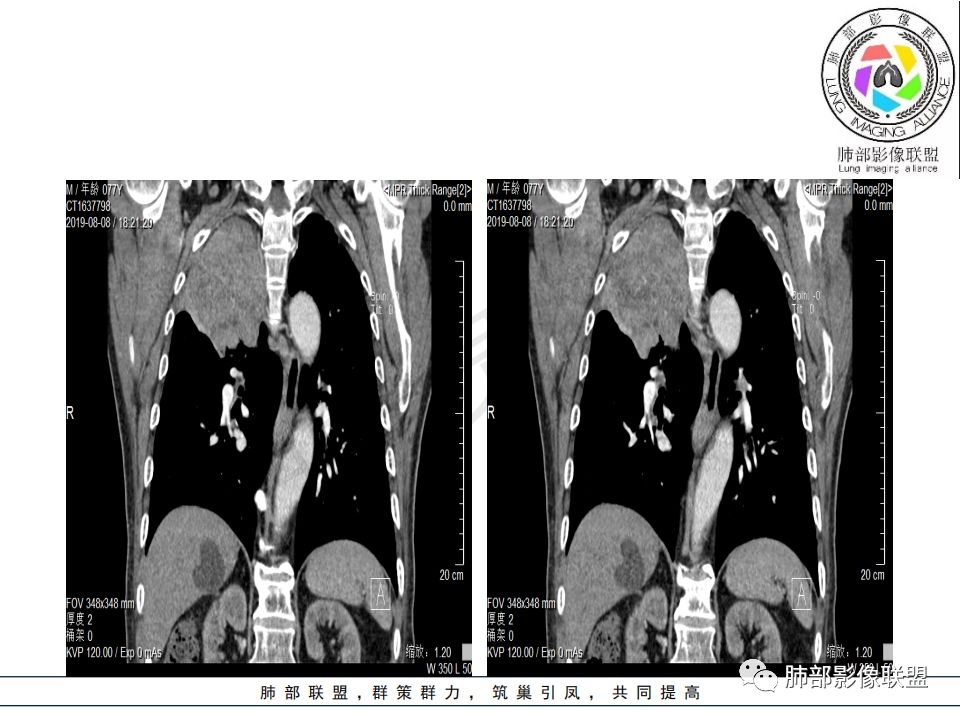

病理结果:腺癌,考虑来源消化道

1.右肺上叶较大块影,密度不均,轻度强化并见低密度区,所属支气管截断并腔内突入,是符合肺鳞癌的影像学特征和生物学行为的。

2.胃癌常会首先胃旁淋巴结、腹主动脉淋巴结转移,肝脏血行转移,以及双肺多发转移,本例孤立右肺上叶病灶巨大,多有不符。

3.胃癌多血供,患者肺内病灶轻度强化。

4.内镜取材不足的可能性是存在的。